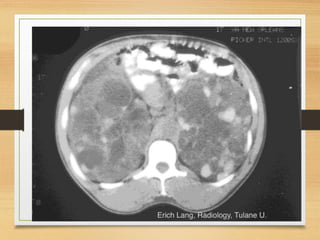

Radiological

• KUB

• U/S

• C.T

• MRU

CASE 4

• A 64-year-old man presents with a 2-month history

of painless visible haematuria, hypertension, weight

loss, loin swelling and anaemia. What is the most

likely diagnosis?